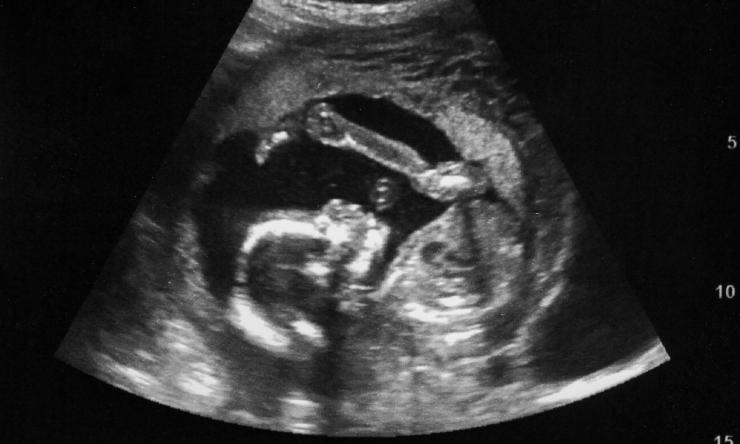

The Perinatal Surgery Fellowship is a two-year program, which trains pediatric surgeons and obstetricians with expertise in maternal-fetal medicine to care for fetal patients with complex diseases such as twin-twin-transfusion syndrome (TTTS), amniotic band syndrome, twin-reversed-arterial-perfusion sequence (TRAP), lung masses, diaphragmatic hernia, urinary tract obstruction, abdominal wall malformations, neural tube defects, congenital tumors, neck masses, congenital cardiac abnormalities and tongue and mouth tumors.

Fellows completing this program gain enhanced understanding of all aspects of fetal care and therapy, including fetal diagnosis (ultrasound, echocardiography, MRI, genetics), perinatal management and surgical techniques (open and minimally invasive techniques).

Pediatric surgeons accepted into this fellowship will be educated in the obstetric aspects of fetal care including comprehensive ultrasound assessment and MRI evaluation of the fetus, placenta and uterus, fetal heart rate monitoring, antepartum fetal biophysical monitoring and evaluation, and surgical procedures currently performed by MFM physicians such as intrauterine blood transfusion, laser ablation of placental blood vessels, radiofrequency ablation of abnormal tissue, bladder and chest shunt procedures, fetal cystoscopy, posterior urethral valve and ureterocele surgery, chorionic villus sampling, and amniocentesis